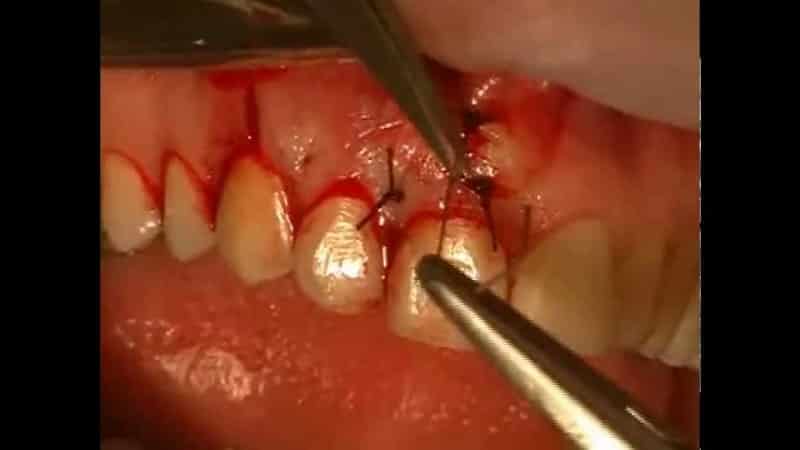

- Подготовка области. Врач обеспечивает удобный доступ к верхушке зуба. Сначала выполняется надрез десны, после чего лоскут ткани отгибается, открывая доступ к челюстной кости. Затем стоматолог находит участок кости корня, где было выявлено образование. В этом месте хирург делает небольшое отверстие с помощью стоматологических боров и бормашины.

- Резекция зуба. Врач использует отверстие для нахождения верхушки корня и расположенной рядом кисты. С помощью бормашины хирург производит резекцию (удаление) верхушки корня. Затем с помощью пинцета удаляется обломок верхушки и связанное с ней патологическое образование из образовавшейся раны.

- Наложение швов. Завершающим этапом является санация ротовой полости и промывание раны антибактериальным раствором. После этого врач сшивает слизистую десны, устанавливая между швами дренаж для оттока крови и сукровицы. Затем на полчаса к области операции прикладываются холодные предметы, и накладывается давящая повязка. Это помогает уменьшить послеоперационный отек и гематому в зоне резекции. Кушать можно не ранее чем через 3-4 часа после процедуры. Дренаж удаляется через несколько дней.